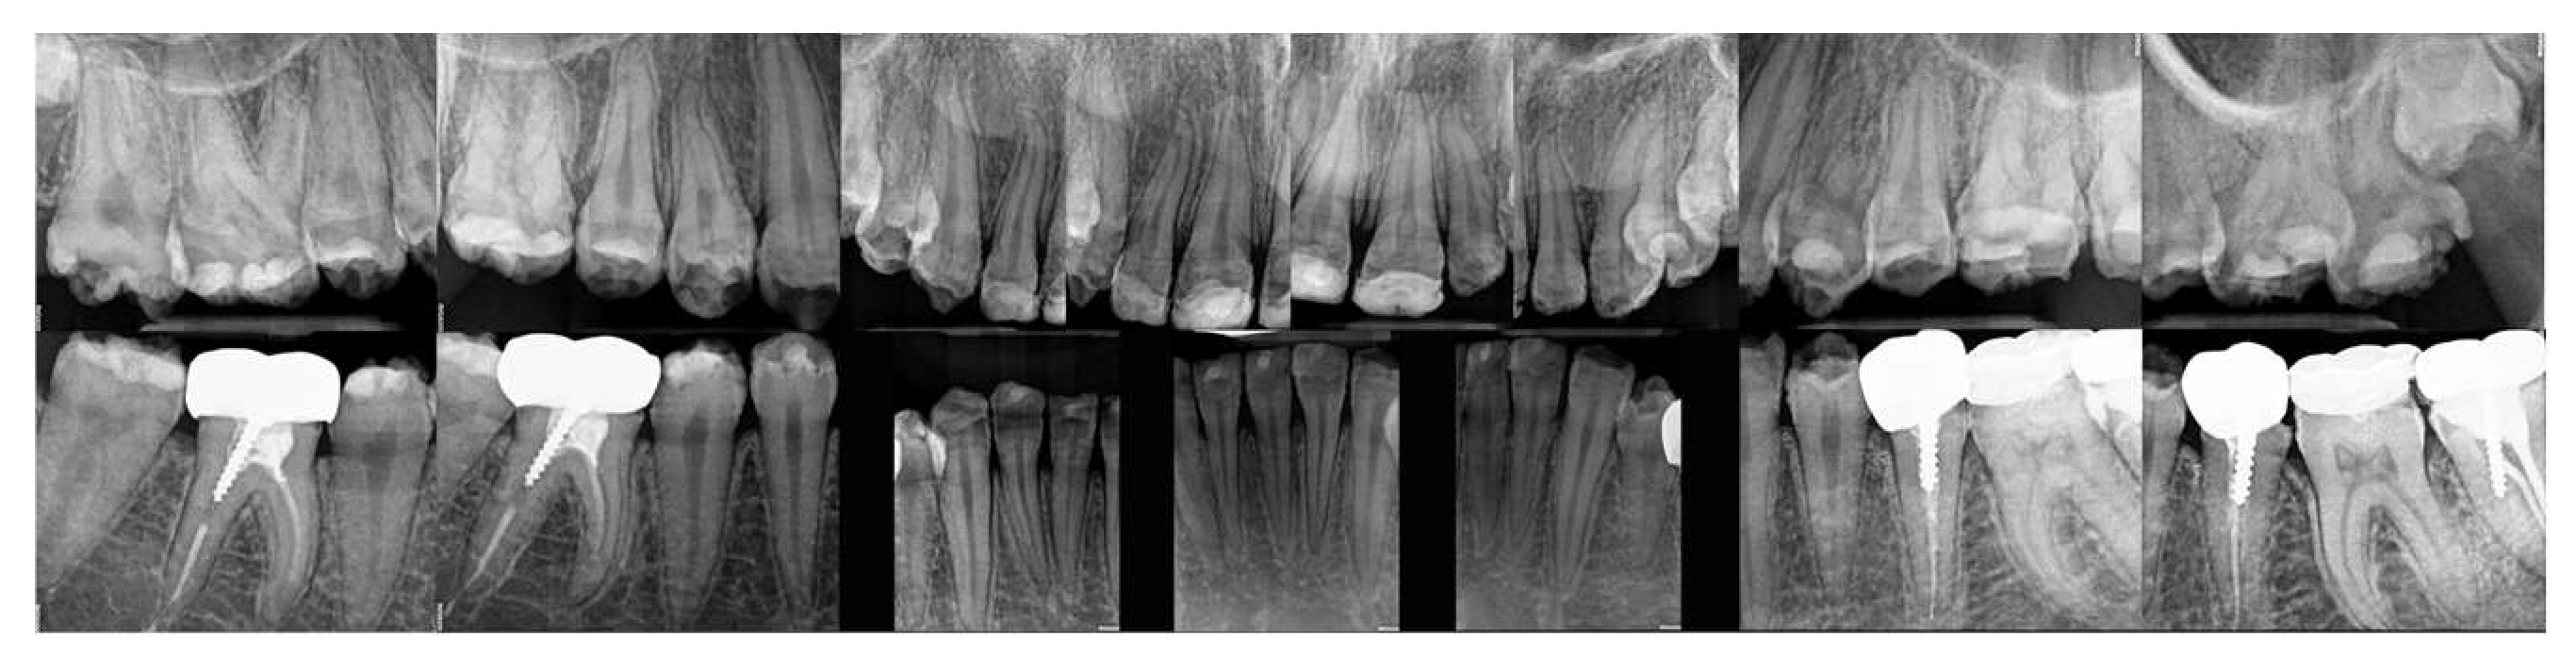

2.2. Clinical Examination

2.3. Radiographic Examinations